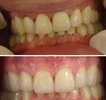

Zirkonyum uygulamalar

Porselen uygulamaları

Laminate veneer